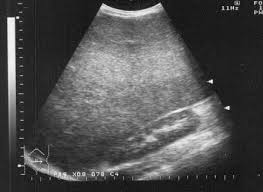

Heatomegaly

Hepatomegaly